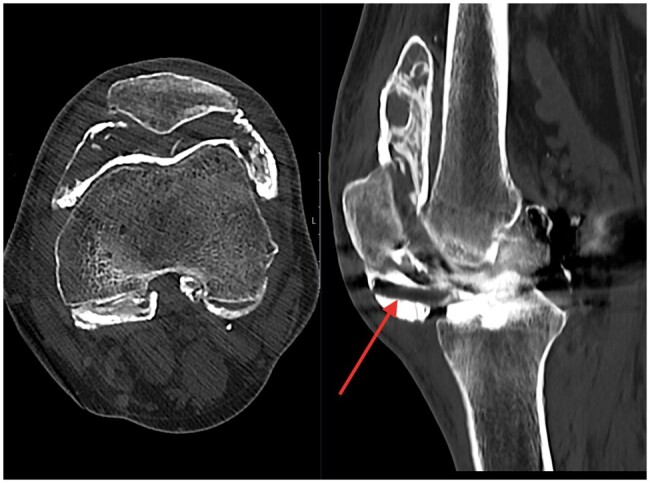

We present the radiological findings in the case of a failed unicompartmental knee arthroplasty (UKA). Although uncommon, these features are highly specific for implant failure and are an indication to consider revision. The aim of this case report is to highlight these characteristic appearances across multiple imaging modalities to both surgeons and radiologists should they encounter this in their practise.

Abstract Image